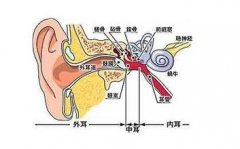

中耳炎有哪些常见的症状

中耳炎,就是我们日常生活中所说的“烂耳朵”,其实是鼓室粘膜的炎症,由细菌入侵了鼓室所致。中耳炎的症状其实非常明显,在生活中很容易看出。... [详情] 文章日期 :16-11-05